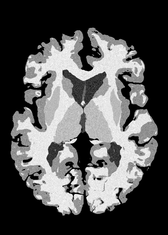

4.2 Registration to a 100 micron ex-vivo brain MRI volume

To showcase the efficacy of our method on real large scale images, we register a 250 in-vivo MRI image (Lüsebrink et al., 2017) to a 100 ex-vivo FLASH human brain volume (Edlow et al., 2019). This represents an inverse problem with more than 11.2B optimizable parameters (compared to 20M for clinical datasets), or 44.8GB of GPU memory. The entire problem does not fit on most GPUs, necessitating distributed multimodal registration. We optimize a composite transform - affine followed by a diffeomorphic mapping; details can be found in Section E.1. Multimodal deformable registration took 58 seconds on 8 NVIDIA A6000 GPUs, which is unprecedented at this resolution. Fig. 6 shows qualitative results, highlighting the ability to register highly detailed structures such as cerebellar white matter; these structures are not visible at macroscopic scales. The resultant advantages of performing registration at this scale can allow researchers to characterize the neuroanatomy at microscopic resolutions and allow morphometric analysis of cortical layers and subcortical nuclei among other structures.